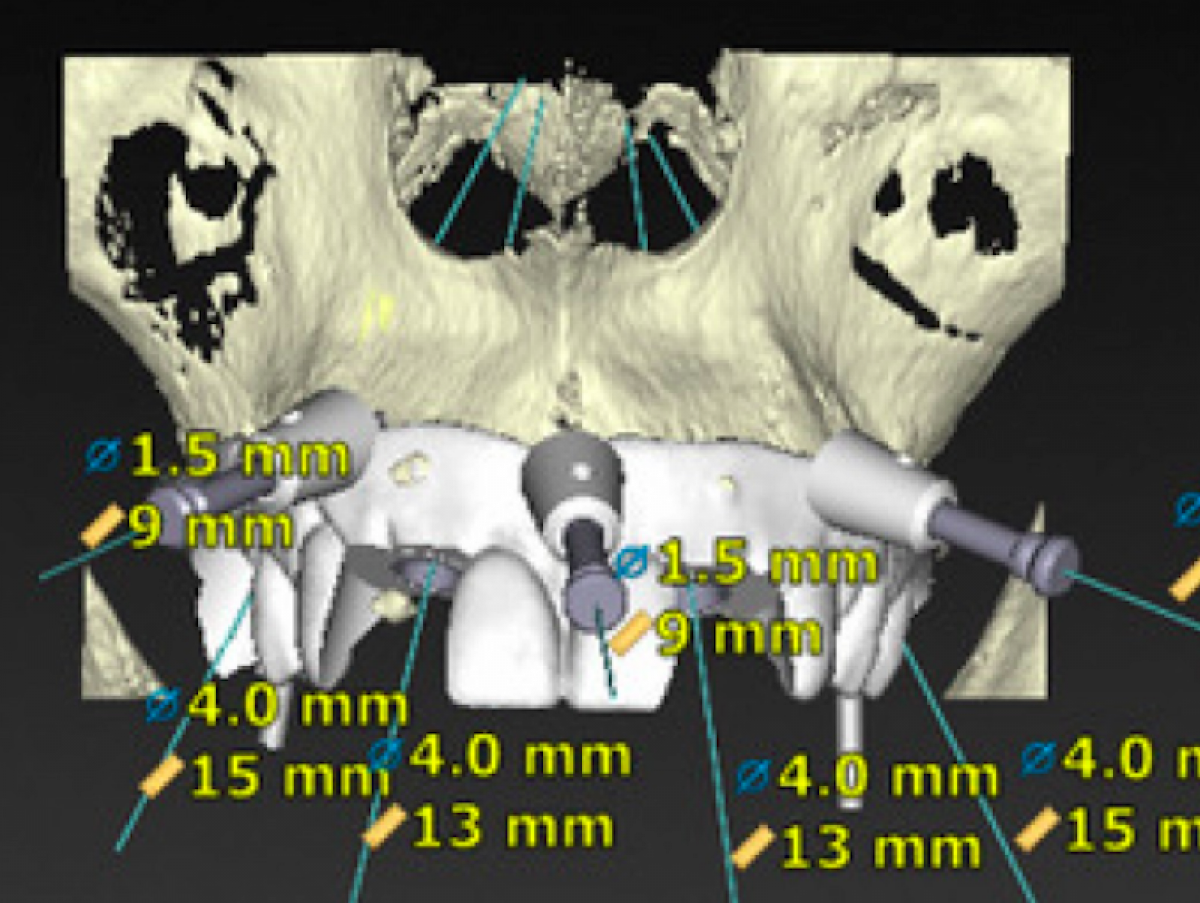

The X-ray images were studied using the Nobel Guide, later due to two implant surgeries (Figure 1).

Prior to surgery, the provisional prostheses were digitally designed based on implant planning and made by milling to CAD / CAM. The surgery day, the implants were inserted using surgical templates and, subsequently, the provisional prostheses were fixed to the provisional abutments, finished and subjected to immediate loading.